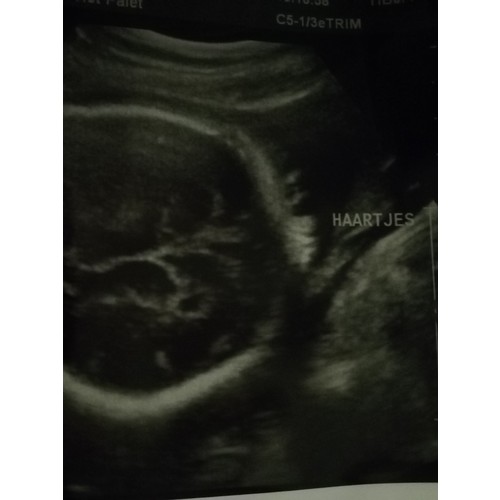

Dit was mijn echo met ‘haartjes’, voor mij abracadabra maar voor de echoscopist heel duidelijk.. onze dochter afgelopen woensdag geboren, lekker veel haartjes (donker) en al echte mooie wenkbrauwen 🥰